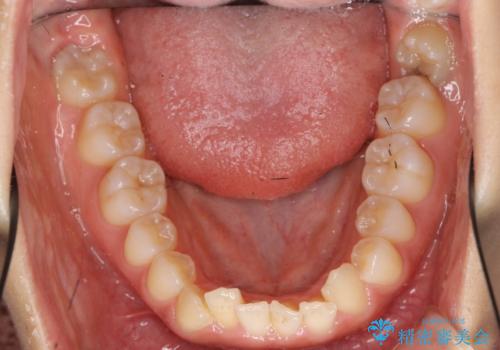

前歯のがたつき インビザラインで 下の奥歯を後ろに下げる

- 上下の前歯のがたつきを主訴に来院。

骨格的に受け口の傾向があり、下の奥歯が前方にに位置しており、下の前歯が特にがたつきが大きい状態でした。

下の奥歯を後ろに下げて下の前歯が前方に出ないように治療しました。

矯正用ミニスクリューを用いて治療しています。

奥歯のかみ合わせの前後的なずれをそのままにして治療すると、前歯が突き上げるような状態になってしまいます。

ただその場で並べるのではなく、症状によっては奥歯を後ろに下げる必要があります。